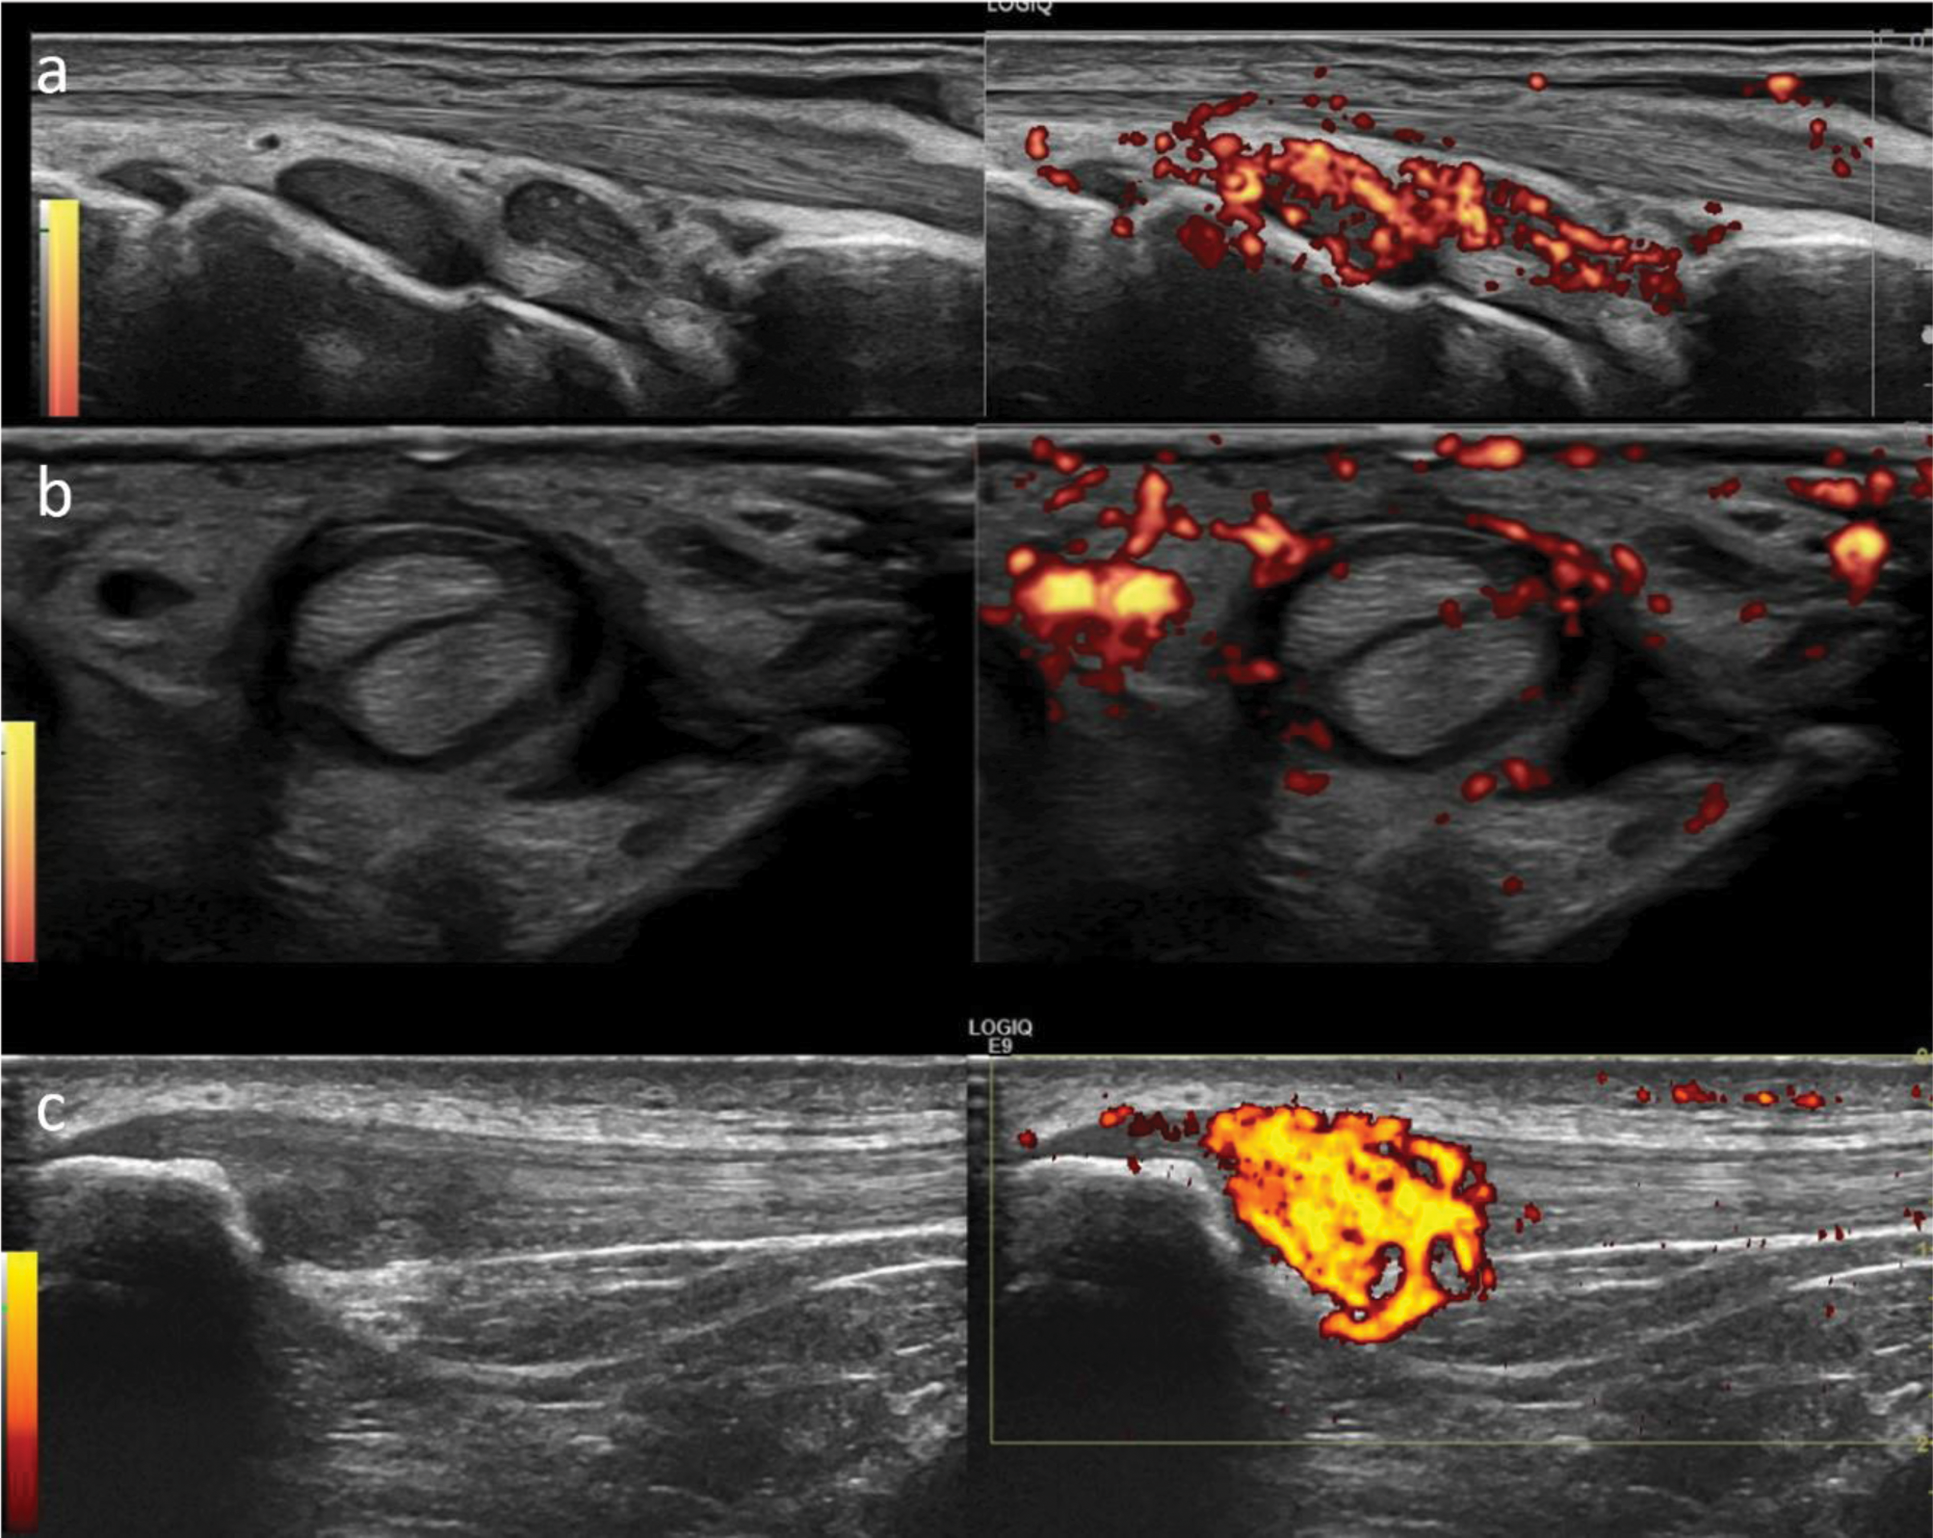

Results: This multi-centre study included 101 patients: 48 with ICI-arthritis and 53 with ICI-arthralgia. The majority of patients had a diagnosis of melanoma (32.7%) or lung cancer (21.8%). Monotherapy (91.1% of patients) with pembrolizumab (46.5%) and nivolumab (30.7%) were the most commonly used treatments. The overall mean age was 63.6 years, with ICI-arthritis patients being older (69.4 years) than ICI-arthralgia patients (64.4 years, p=0.015). C-reactive protein (CRP) levels and early morning stiffness were similar between the two groups. Corticosteroid use was more common in ICI-arthritis patients (59.6%) than in ICI-arthralgia patients (32.7%, p=0.009). There were no significant differences in autoantibody positivity (CCP, ANA, RF) or other immune-related adverse events (44.2% vs. 47.7%, p=0.84). ICI-arthritis patients had monoarthritis (n=18), oligoarthritis (n=15), or polyarthritis (n=15). A high proportion of ICI-arthralgia patients had ultrasound-detected subclinical synovitis (47.2%), tenosynovitis (18.9%), and enthesitis (24.5%) despite the absence of joint swelling (Table 1). Overall, ultrasound synovitis was more frequent in ICI-arthritis than in ICI-arthralgia (93.8% vs. 47.2%, p<0.001), particularly in the wrists (56.3% vs. 20.8%, p<0.001) and knees (54.2% vs. 13.2%, p<0.001), which were the most frequently affected joints. Tenosynovitis was also more common in ICI-arthritis (52.1% vs. 18.9%, p<0.001), most frequently seen at the extensor carpi ulnaris (22.9% vs. 9.2%, p=0.1). However, there was no significant difference in the prevalence of “active” enthesitis (31.3% vs. 24.5%, p=0.51), which was most common at the lateral epicondyles in both groups. Bone erosions were more prevalent in ICI-arthritis than in ICI-arthralgia (25% vs. 7.5%, p=0.027), most commonly seen at the wrists (ulnar styloid) in both groups (16.7% vs. 5.7%, p=0.11). A pictorial example of joint synovitis, tenosynovitis and enthesitis in patients with ICI-arthritis/arthralgia is shown in Figure 1.

Pictorial examples of joint synovitis, tenosynovitis and enthesitis in patients with ICI-arthritis

Legend . Images show wrist synovitis (a), 3rd finger flexor tendon tenosynovitis (b) and proximal patellar tendon enthesitis (c).